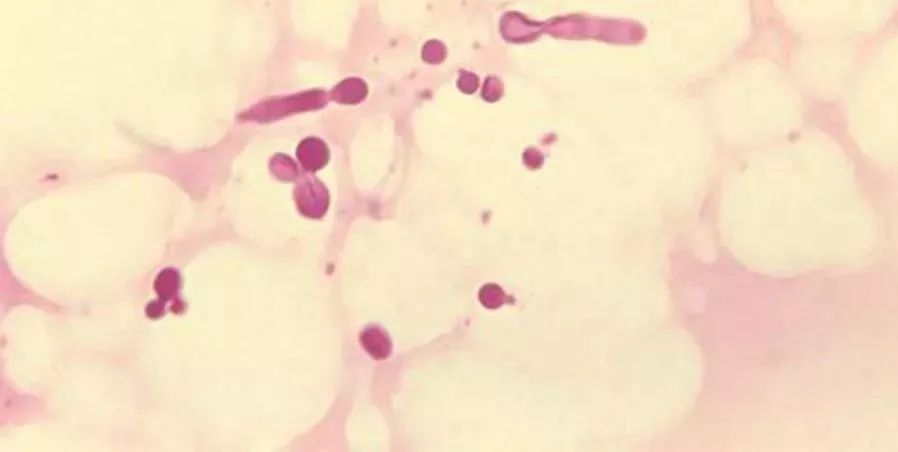

抗真菌:有實驗證明,乳鐵蛋白可以殺死真菌(須癬毛癬菌、白色念珠菌),但是作用機理待研究。